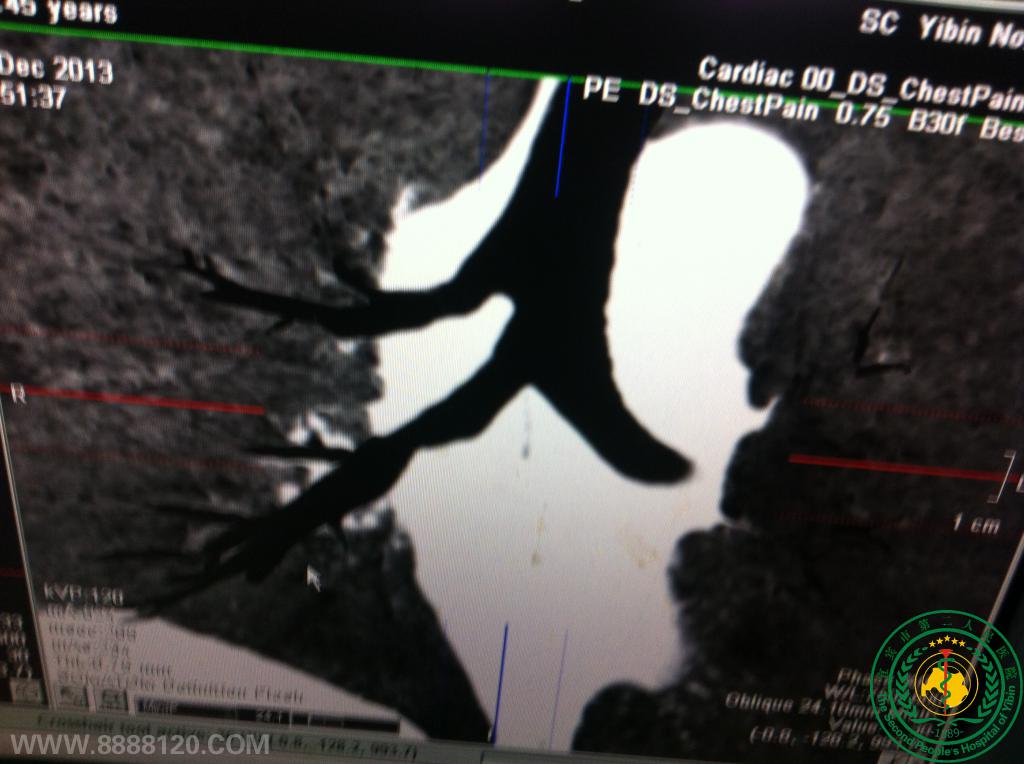

宜宾市第二人民医院胸心外科成功救治一名右肺上下叶支气管完全断裂重伤员(右上叶支气管发育异常)

宜宾市第二人民医院胸心外科成功救治一名右肺上下叶支气管完全断裂重伤员(右上叶支气管发育异常)6177